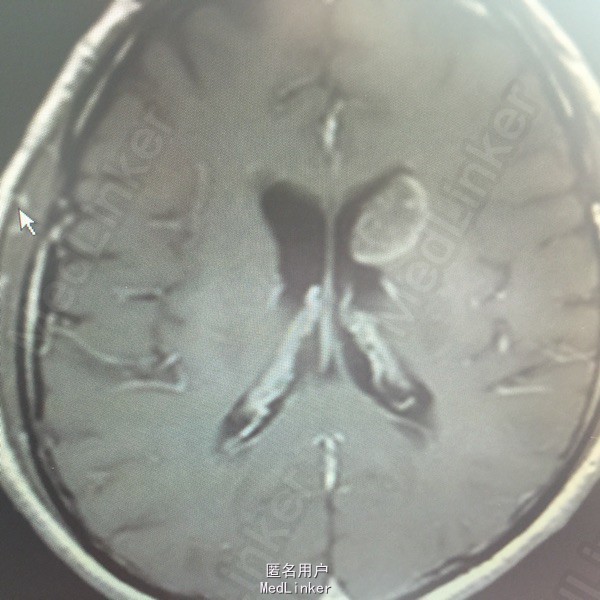

男,54岁,以头痛半个月入院。 现病史:半个月前无诱因头痛,呈胀痛,无呕吐,无意识障碍,病来咳嗽、咳痰,体重减轻约5斤,无发热。 既往史:无特殊。

查体:BP:150/100mmHg,神清语明,两瞳孔等大正圆,直径约3.0mm,光敏,四肢肌力5级,肌张力正常,腱反射艹,左侧共济运动阳性,病理征阳性,脑膜刺激征(-)。 辅查:见下:

肺癌脑转移。 影像解读(影像如何解读是临床工作中非常重要的一环)。 左侧额叶近皮质长Tl长T2信号,局部颅骨缺损,右侧枕叶不规则病灶,TlWl呈中心呈等信号,周围高信号,T2Wl呈高低混杂信号,伴大片水肿,相邻侧脑室后角、胼胝体受压。增强呈不规则环环强化。 已进行局部放疗治疗。